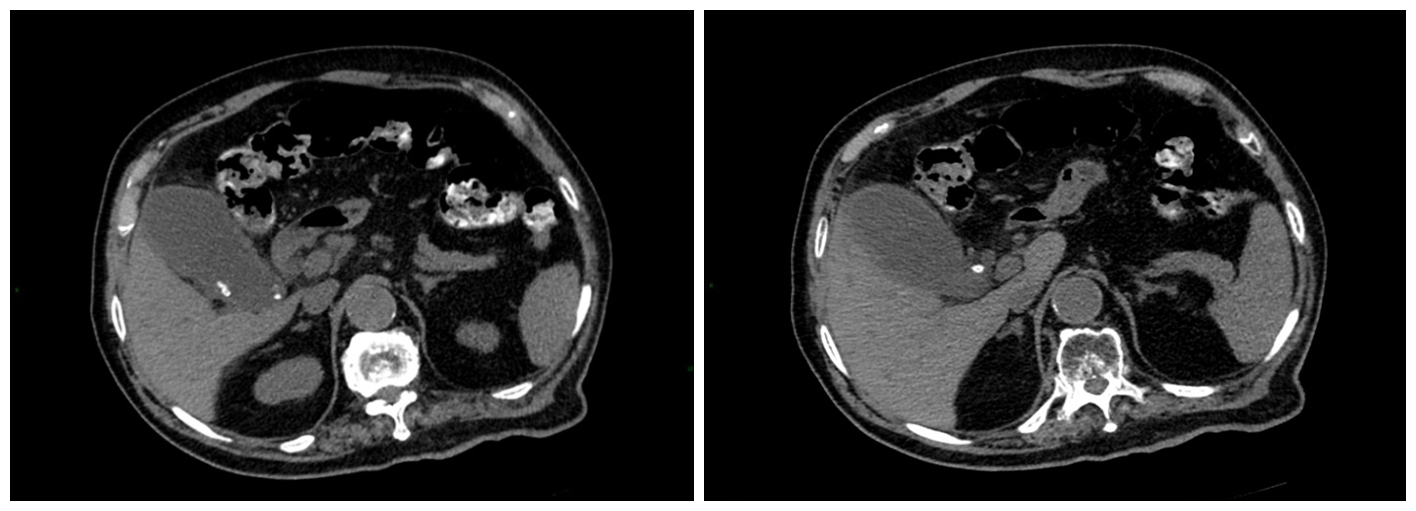

患者术前上腹部CT检查提示:胆囊明显增大,大小约5*10cm,壁厚毛糙,胆囊内及胆囊颈-胆囊管内可见结节状结石影,直径约7mm;刘大爷的胆囊已经肿胀的像小气球一样,比正常胆囊大一倍。